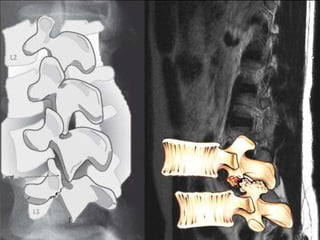

Póstero –lateral

Foraminal

Póstero –mediana

Canal

Neurogênicas

Espondilogênicas

(McGill, 2007)